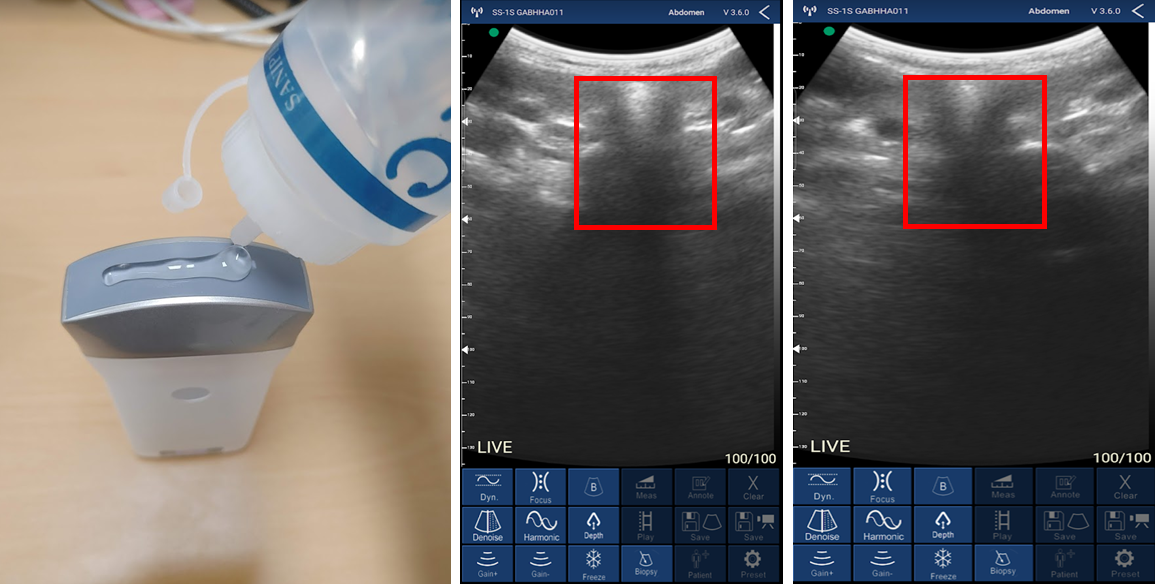

이제 갑상선을 봐야겠죠? 초음파에 젤을 바르고 갑상선 위치에 대어 봅니다. 휴대폰에 갑상선이 출력된 것을 확인할 수 있습니다.